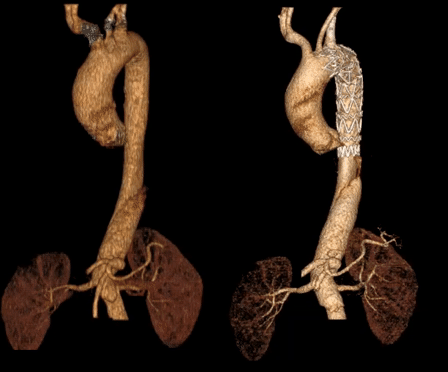

主动脉CTA详解:Standford B型主动脉夹层,破口位于胸降主动脉,破口直径7mm,假腔位于真腔前缘;主动脉管壁周围少许渗出影,可见壁内血肿、血栓、溃疡突起,近端血肿已累及LSA根部,LSA与LCCA距离仅8.5mm,左椎动脉优势;弓上三分支血流显影可,内脏区腹腔干动脉、肠系膜上动脉及右肾动脉起自假腔,左肾动脉起自真腔。

术后1周复查主动脉CTA显示胸主动脉血管重塑良好,开窗支架形态正常。远端内脏区显影良好。